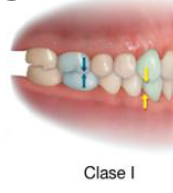

En aquest cas podem veure que l'oclusió a nivell sagital per la part posterior és de classe I, és a dir una neutroclusió és quan la cúspide mesiovestibular del 1r molar superior oclou en el solc bucal del 1r molar inferior, en aquest cas el caní no té contacte.

NEUTROCLUSIÓ